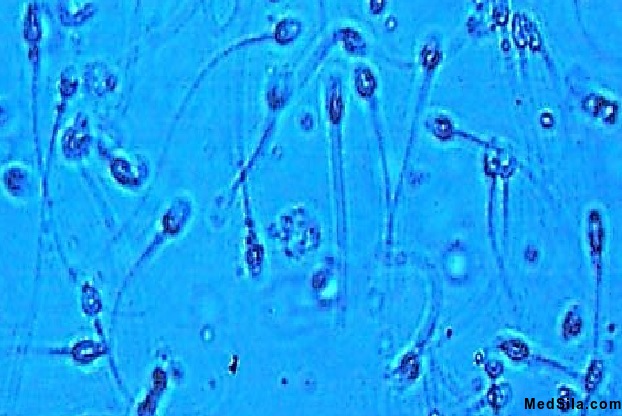

Исследование спермы

Свежедоставленную сперму сразу же берут для исследования. При этом в направлении отмечают фамилию, имя, отчество пациента и объем собранной спермы. Объем спермы обычно достигает до 2 мл (иногда объем спермы может составлять до 6 мл). «На глаз» оценивают цвет спермы (в норме сперма беловатого цвета), в нормальной сперме не должно содержаться эритроцитов (кровяных клеток), наличие этих клеток может свидетельствовать о серьезной патологии, встречается при травмах половых органов), лейкоцитов в минимальном количестве до 106 в 1 мл. Увеличение количества лейкоцитов говорит, о наличии воспалительного процесса в организме.

Так же к общим показателям спермограммы относятся:

- ph спермы (7.2 – 8.1)

- Вязкость (до 1,9 см)

- Общее количество сперматозоидов в эякуляте (сперме) не менее 40 млн. Количество сперматозоидов в 1 мл. – до 20 млн/мл. После оценки общих параметров врач лабораторной диагностики проводит микроскопическое исследование (под микроскопом). Под объективом микроскопа врач – лаборант оценивает подвижность сперматозоидов (оценивается быстрота поступательных движений), форму сперматозоидов (наличие всех частей у активного сперматозоида - головки, шейки (средняя часть), хвоста), жизнеспособность (наличие незначительного количества мертвых сперматозоидов может носить временных характер, например, при тяжелых отравлениях), наличие склеенных (агглютинированных) сперматозоидов (в норме их быть не должно, иногда встречается при иммунной патологии).

В спермограмме отмечаются амилоидные тельца и лецитиновые зерна (обычно встречаются при снижении функции предстательной железы), а также слизь в небольшом количестве. Иногда для более подробного анализа спермы проводят биохимический анализ с определением кислой фосфатазы, лимонной кислоты, цинка, фруктозы и др.